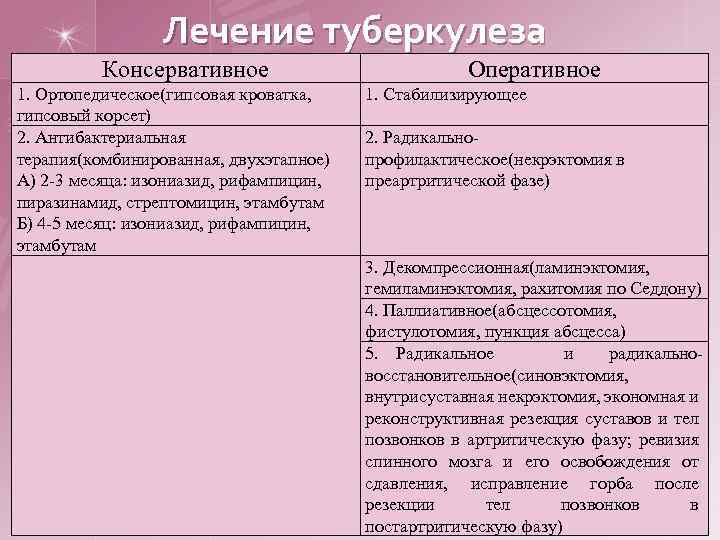

Лечение туберкулеза Консервативное 1. Ортопедическое(гипсовая кроватка, гипсовый корсет) 2. Антибактериальная терапия(комбинированная, двухэтапное) А) 2 -3 месяца: изониазид, рифампицин, пиразинамид, стрептомицин, этамбутам Б) 4 -5 месяц: изониазид, рифампицин, этамбутам Оперативное 1. Стабилизирующее 2. Радикальнопрофилактическое(некрэктомия в преартритической фазе) 3. Декомпрессионная(ламинэктомия, гемиламинэктомия, рахитомия по Седдону) 4. Паллиативное(абсцессотомия, фистулотомия, пункция абсцесса) 5. Радикальное и радикальновосстановительное(синовэктомия, внутрисуставная некрэктомия, экономная и реконструктивная резекция суставов и тел позвонков в артритическую фазу; ревизия спинного мозга и его освобождения от сдавления, исправление горба после резекции тел позвонков в постартритическую фазу)